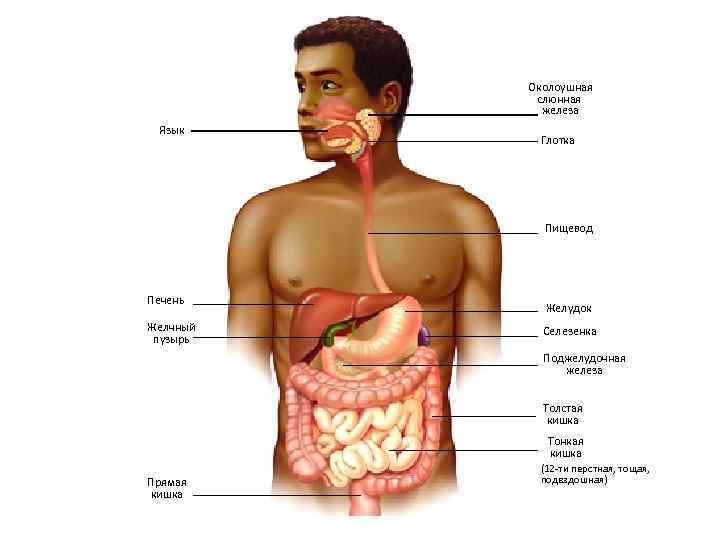

Околоушная слюнная железа Язык Глотка Пищевод Печень Желчный пузырь Желудок Селезенка Поджелудочная железа Толстая кишка Тонкая кишка Прямая кишка (12 -ти перстная, тощая, подвздошная)